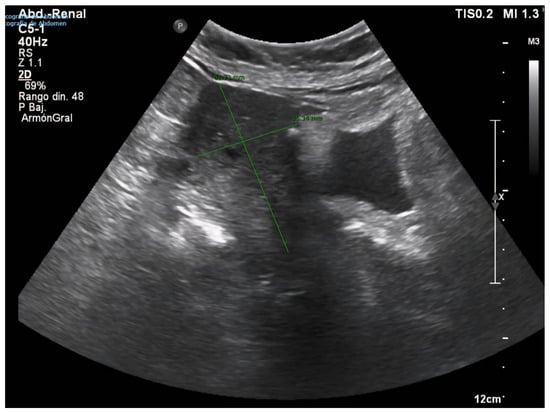

2. Case Presentation